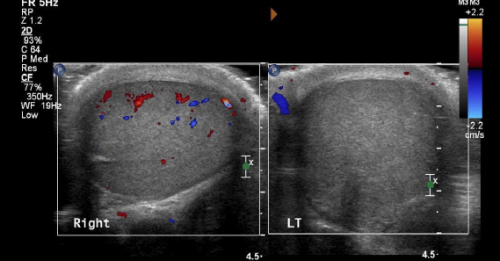

5 Tips on Testicular Torsion

A 20-year-old healthy man arrives at the emergency department at 4 a.m. complaining of one hour of…